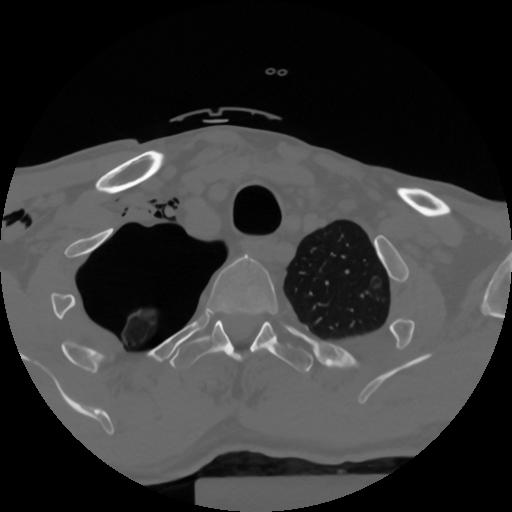

12 P.BLANDAS,,Vol,0.5,P.BLANDAS,,